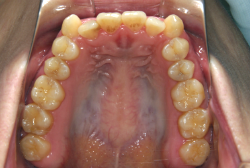

「歯並びの凸凹を直したい」という主訴で来院したケースです。診断の結果、たしかに「叢生」という隙間が足りないと言うことが原因の凸凹症例でした。

しかし、それ以上に問題なのは「前歯の噛み合い方が深すぎる」という症状で、初診の歯の正面写真を見ると下の前歯が全く見えません。こういう症状を矯正学では「過蓋咬合(かがいこうごう)」と言います。過蓋咬合を放置すると、将来的に顎関節に悪影響を与えるとされており、顎関節症の原因因子の一つです。また下の前歯の先端が、上の前歯の裏側の歯茎と強く接触するため、歯周病の原因にもなります。

検査の結果、凸凹が軽症なため非抜歯で矯正すること可能と判断、マルチブラケット装置にて治療しました。治療後は歯並びが綺麗になっただけでなく、噛み合わせ的にも正しい状態が確立しています。